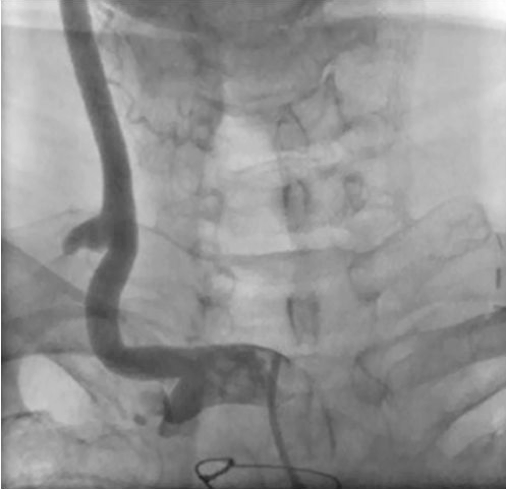

Figure 1. Angiography at the outside hospital reveals proximal left subclavian occlusion and a patent LIMA-LAD graft (click thumbnail to view larger image).

At the time of the present admission at the outside hospital, angiography revealed a proximal total left subclavian occlusion with a patent LIMA graft (Figure 1). A percutaneous approach to treat the lesion was attempted by a vascular surgeon attending. Unfortunately, the lesion could not be crossed with a retrograde or antegrade approach using a 0.035˝ stiff-angled Glidewire guide catheter (Terumo Medical Corporation). On the retrograde attempt via the left brachial artery, a subintimal dissection plane was created. With a failed percutaneous approach, the patient underwent a left SCA-CCA bypass surgery with an 8 mm ringed polytetrafluoroethylene (PTFE) graft.